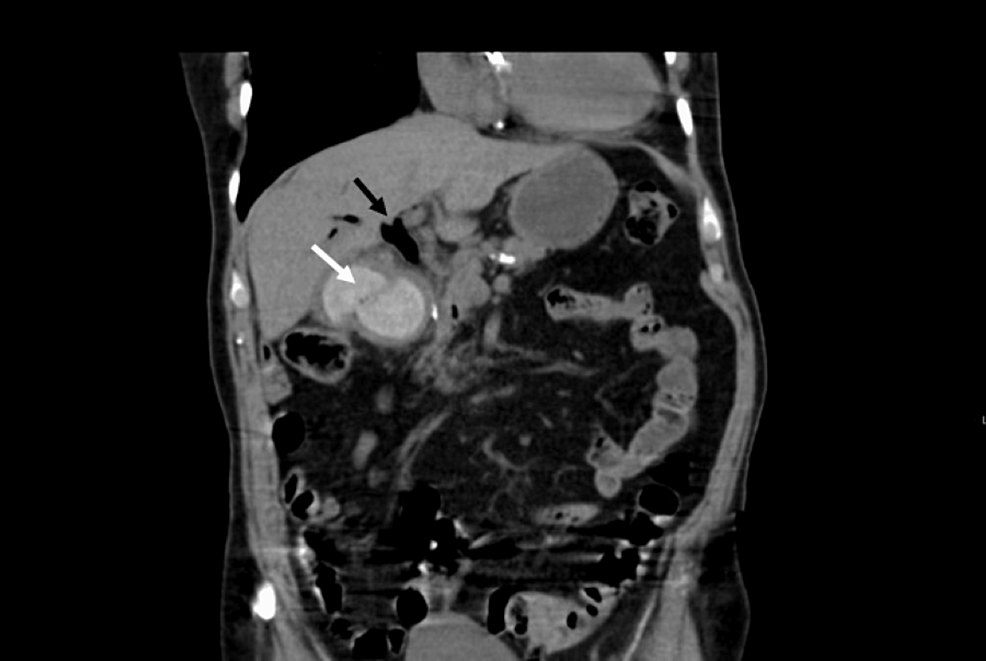

On admission, the patient’s blood results were seen (Table 2). He was treated with intravenous fluids, antiemetics, and analgesia. On day 3 of admission, his OGD showed a large amount of black fluid filling the stomach, severe oesophagitis, and large non-bleeding ulceration with a large brown foreign body in D1, causing gastric outlet obstruction. The foreign body could not be extracted during the OGD. Subsequently, the patient had a CT abdomen and pelvis with contrast, which revealed that he had a gallstone eroding through his gallbladder into D1/2 (Figures 3–4). On day 4, his Hb had dropped to 80 g/l from 110 g/l the previous day, and he was immediately resuscitated with a blood transfusion. He had a repeat OGD where the foreign body was identified as a gallstone. Stone extraction was attempted; however, it was not successful even with the use of an 18-mm balloon and snare. A duodenal stent was subsequently inserted to bypass the obstruction due to the impacted gallstone and to bypass the obstruction. Patency was confirmed by a contrast study, and then the patient gradually recovered and was discharged home.